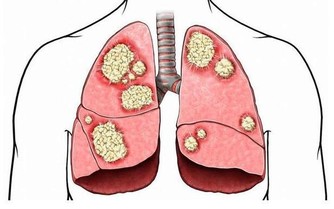

在某些情況下,手臂處的深靜脈血栓會分離出一部分隨血液流動,最終會進入肺部,誘發肺栓塞。